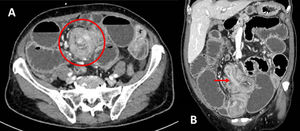

Presentamos el caso de una mujer de 70 años, sin antecedentes médicos de interés ni cirugías abdominales previas, que ingresó por un cuadro de obstrucción intestinal. En la tomografía computarizada se observó una invaginación intestinal íleo-ileal probablemente secundaria a una lesión subyacente, con el característico «signo del donut» o «signo de la escarapela» (fig. 1). Se realizó una laparotomía exploradora urgente. Los hallazgos intraoperatorios se muestran en la figura 2.